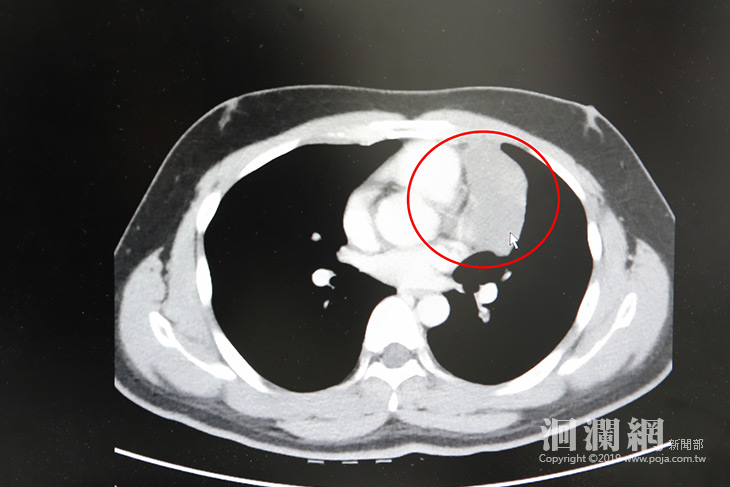

張睿智主任表示,經過電腦斷層掃描後,陳先生的腫瘤為八公分大的胸腺瘤,形狀如雞蛋,不僅離心包膜、血管非常近,執行手術有一定的難度,所以使用達文西手術為陳先生移除腫瘤過程中須小心翼翼地先將前縱膈腔的腫瘤與血管分離,再將腫瘤完整清除乾淨。